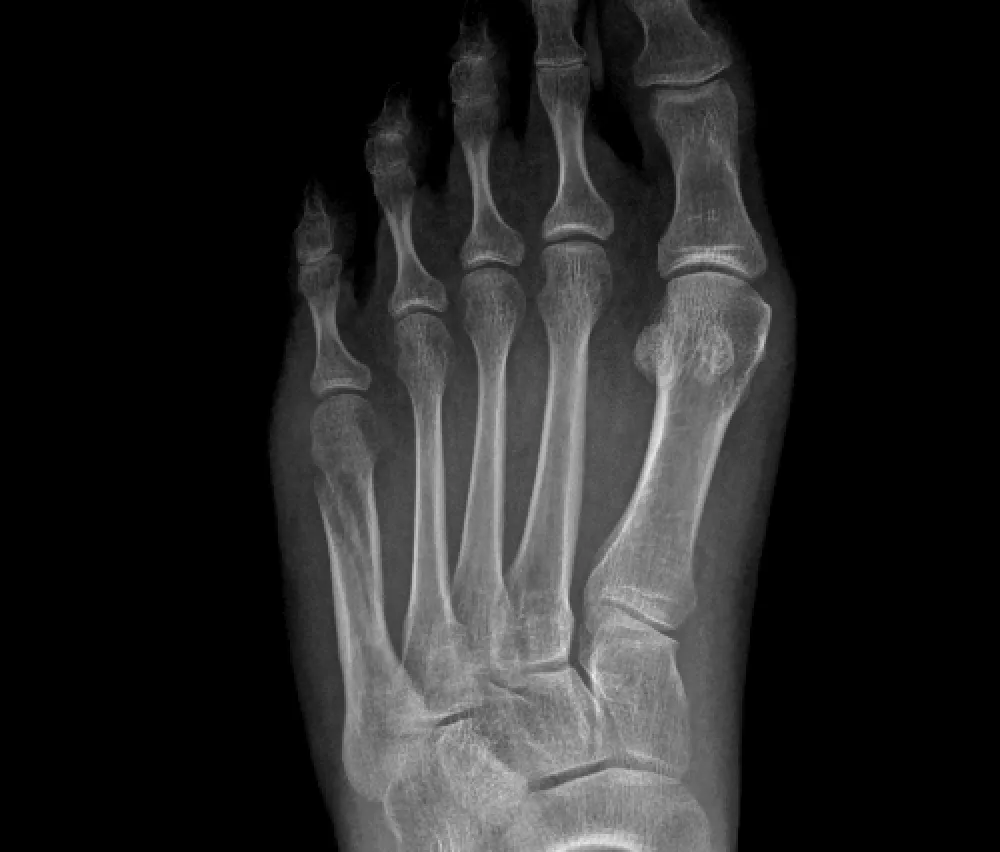

Metatarsal Fractures

These fractures affect the long bones of the foot, known as metatarsals. They can result from direct trauma or excessive pressure, such as dropping a heavy object on the foot.